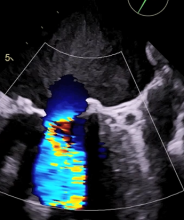

In the following video, the authors briefly show the aortic TAVR and the transseptal VIV Edwards SAPIEN 3® TMVR. The aortic TAVR was done with a Medtronic COREVALVE of 26 mm and the mitral TVMR was done with an Edwards SAPIEN 3 29 mm. The final result was optimal with no mitral or aortic regurgitation and with very low mean gradients.